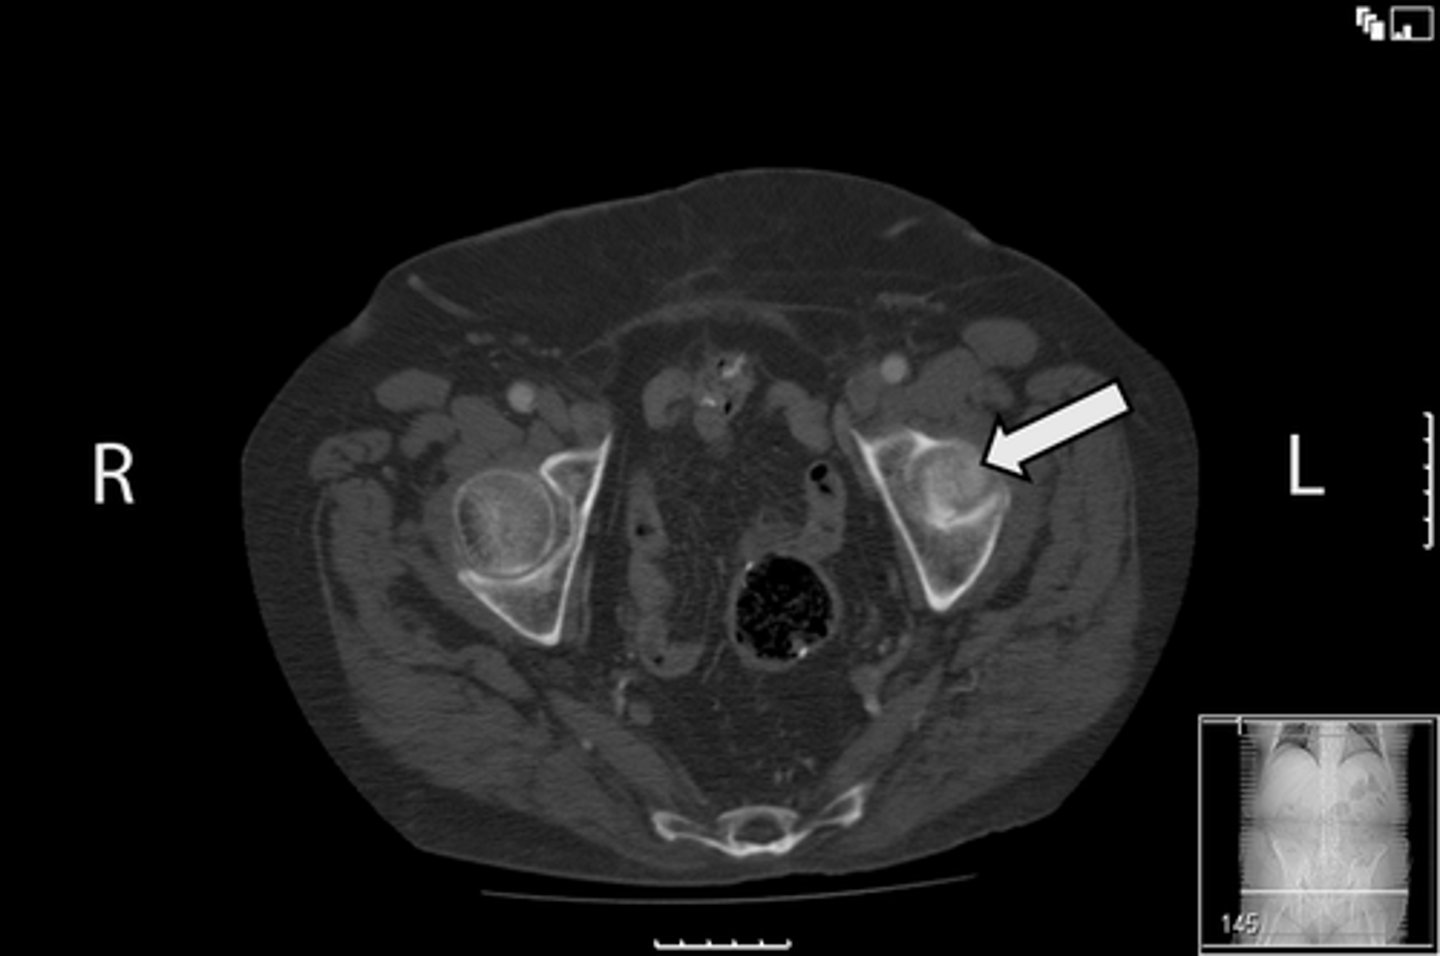

Axial bony pelvis CT

What is the image?

L ilium

What is indicated in the image?

<p>What is indicated in the image?</p>

L sacroiliac joint

R ilium

R sacroiliac joint

Sacrum